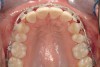

Fig 11. Corticotomy SFOT. A 42-year-old male presented with a history of extraction orthodontic therapy.

Figure 11

Fig 12 (and Fig 13). Incisors were too upright and had severe incisal wear. He was concerned about esthetics of the worn teeth and his insufficient lip support. Progress photo and panorex 9 months after corticotomies were performed on Nos. 6 through 11. Previous extraction sites were reopened orthodontically to improve function and fill lip support. Incisal edges were restored provisionally with composite resin. Note that despite the creation of adequate spaces to replace missing teeth, there is inadequate room for placement of dental implants because of severe tipping of all the anterior teeth. Osteotomy SFOT may have been a better choice because it would have allowed needed alveoloskeletal correction (without excessive tipping) instead of the primarily dentoalveolar correction common in corticotomy SFOT. Restorative dentist: Brad Jones, DDS.

Figure 12

Fig 13 (and Fig 12). Incisors were too upright and had severe incisal wear. He was concerned about esthetics of the worn teeth and his insufficient lip support. Progress photo and panorex 9 months after corticotomies were performed on Nos. 6 through 11.

Figure 13